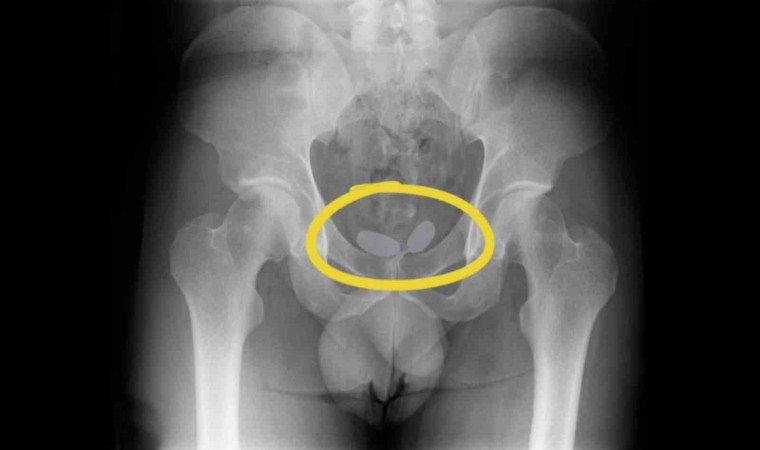

Alınan istihbarat doğrultusunda 2’si yabancı uyruklu toplamda 5 kişi yakalanarak gözaltına alındı. Yapılan röntgen muayenesinde, uyuşturucu kaçakçılarının akıl almaz oyunu ortaya çıktı.

Yapılan röntgen muayenesinde, Alman uyruklu kadının cinsel organında prezervatifler içerisine gizlenmiş uyuşturucular ele geçirildi. Diğer Alman yabancı uyruklu erkeğin ise uyuşturucuları anüsüne gizlediği belirlendi. Yapılan muayene sonrası; 21,19 gram eroin, 12,70 gram kokain, 7,76 gram amfetamin, 7 adet sentetik ecza ele geçirildi.